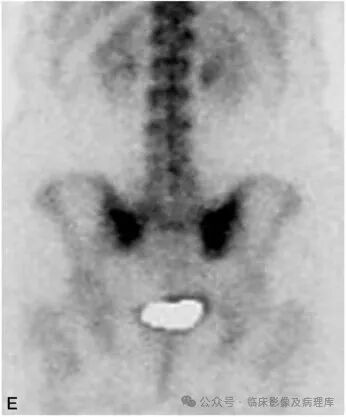

女性,65岁,宫颈癌放疗后。A.骨盆正位片:骨盆诸骨示弥漫性骨质疏松改变,右侧骶骨耳部骨密度减低明显;B.骶骨CT平扫:骶骨弥漫性骨质疏松,双侧骶骨耳部隐见弯曲线样低密度影,周围示片状骨质硬化影。骶骨右前缘示局限性皮质中断;C、D.冠状位SE T1WI和脂肪抑制FSE T2WI示双侧骶骨耳部弯曲线样低信号影,周围见大片状长T1长T2水肿信号;E.核素扫描(后面观):双侧骶骨耳部核素浓聚,以右侧明显